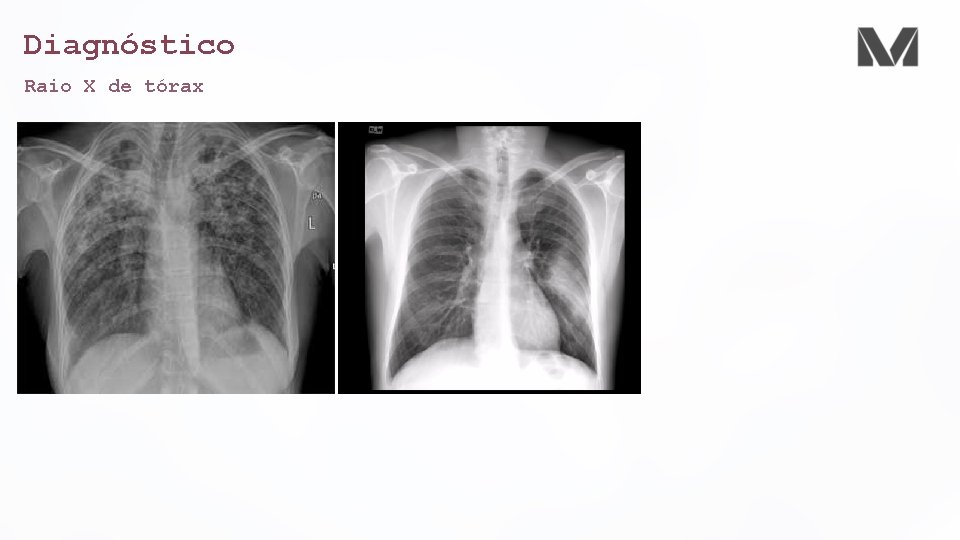

Diagnóstico Raio X de tórax • Obrigatório • Uma consolidação só se torna auscultável quando há menos de 5 cm da pleura visceral • Diagnosticar complicações • Derrames pleurais • Empiemas • Abcessos • Pneumatoceles • Cavitações • Avaliar o padrão • Broncopneumonia • Lobar • Infiltrado intersticial difuso (atípico)

Diagnóstico Raio X de tórax